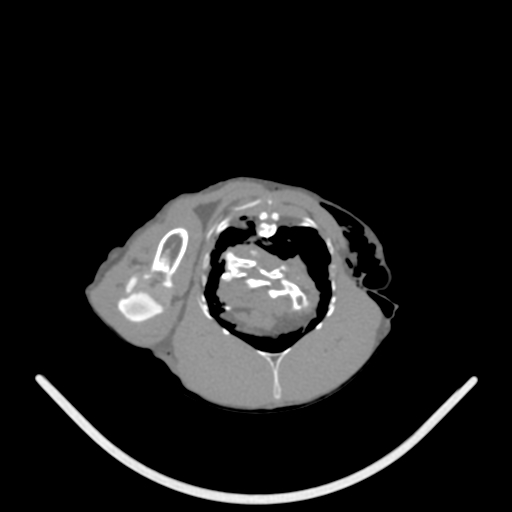

VetTom 8 provides diagnostic quality Computed Tomography (CT) images in a small mobile package. The system is capable of providing at 25 cm field-of-view with high contrast to noise giving you diagnostic confidence for soft-tissue disease and injury.

The modern Through-Silicon-Via (TSV) stacked CT detectors provide high-resolution images with low noise and high contrast, while the 40 cm gantry and 30 cm field-of-view provide additional space and information for your diagnostic needs versus VetTom 8.

The VetTom 32 has a powerful 40 kW generator, 85 cm gantry, 60 cm field-of-view, scans using proprietary batteries and can be moved to where you need imaging, especially when it may be difficult to move the patient.